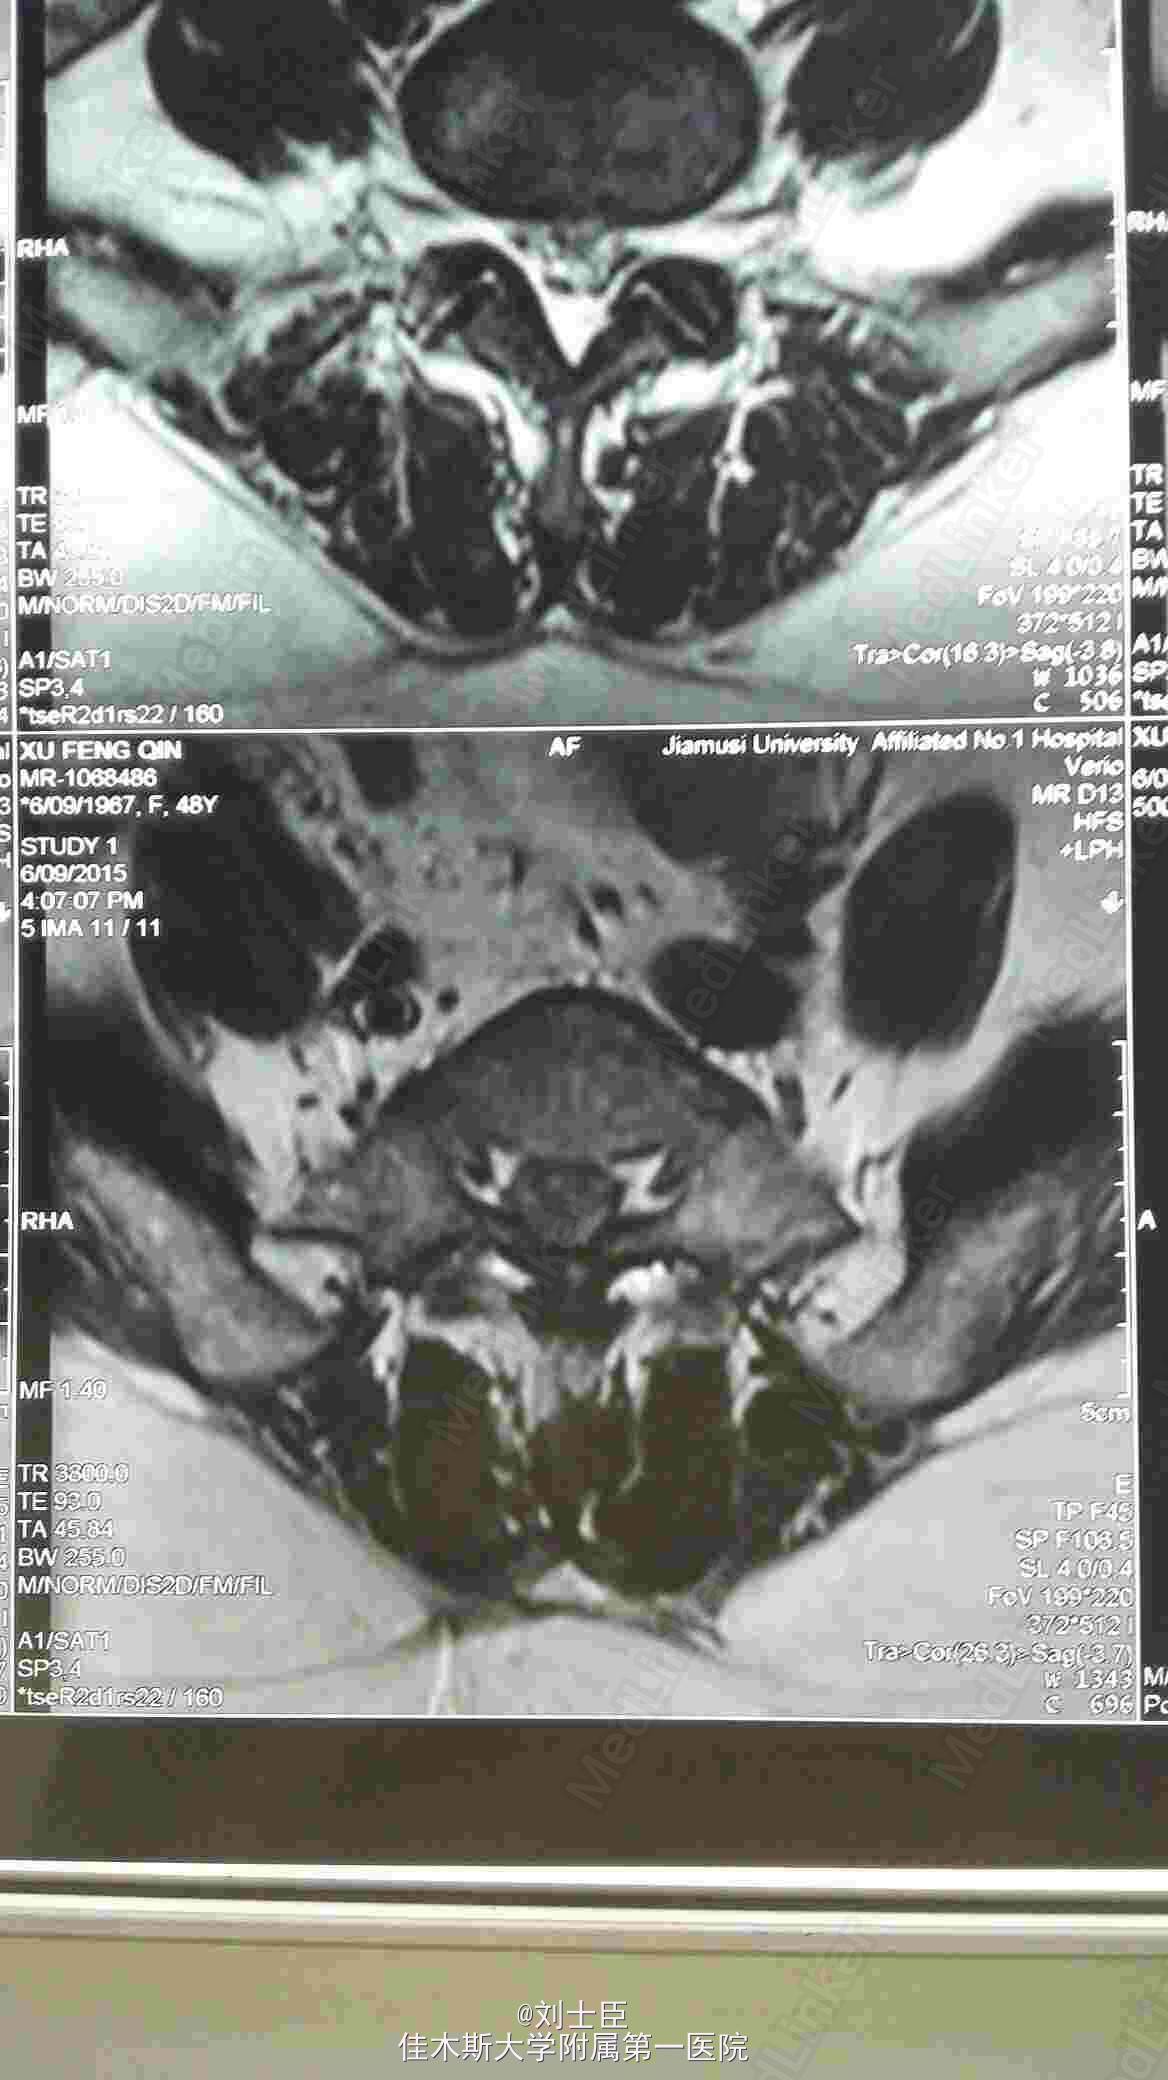

某某,女,43岁。腰痛伴双下肢疼痛1年伴二便失禁7天。

双侧小腿外侧双足及双臀部感觉麻木,双膝反射弱,双踝反射为引出。双下肢肌力进正常。

腰5骶1间盘突出症。马尾综合征。椎间孔镜下游离间盘摘除术纤维环成形术。

病人术后即可刻下地行走自如,直腿抬高实验阴性。3天后拔出尿管,二便正常,双下肢和臀区感觉麻木减轻。